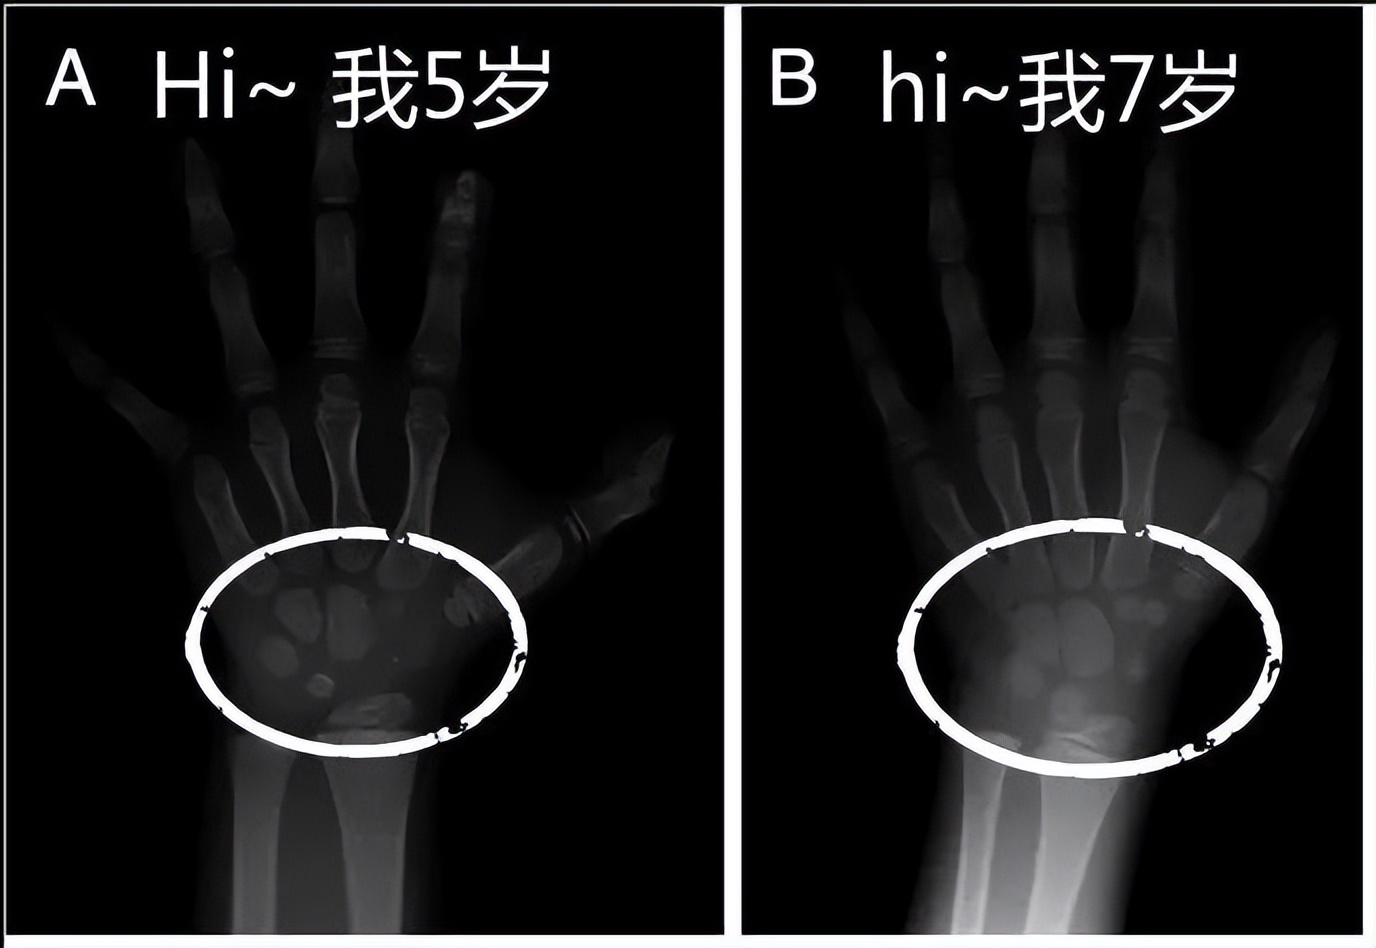

一旦发现孩子身高落后于同龄人,就会带孩子做一系列的检查,其中“骨龄”就是父母很关心的参考指标。

测量骨龄的值与孩子的实际年龄相差1岁左右都视为正常, 只有超过或落后一岁多至二岁,才能表现出早期或落后的发育。